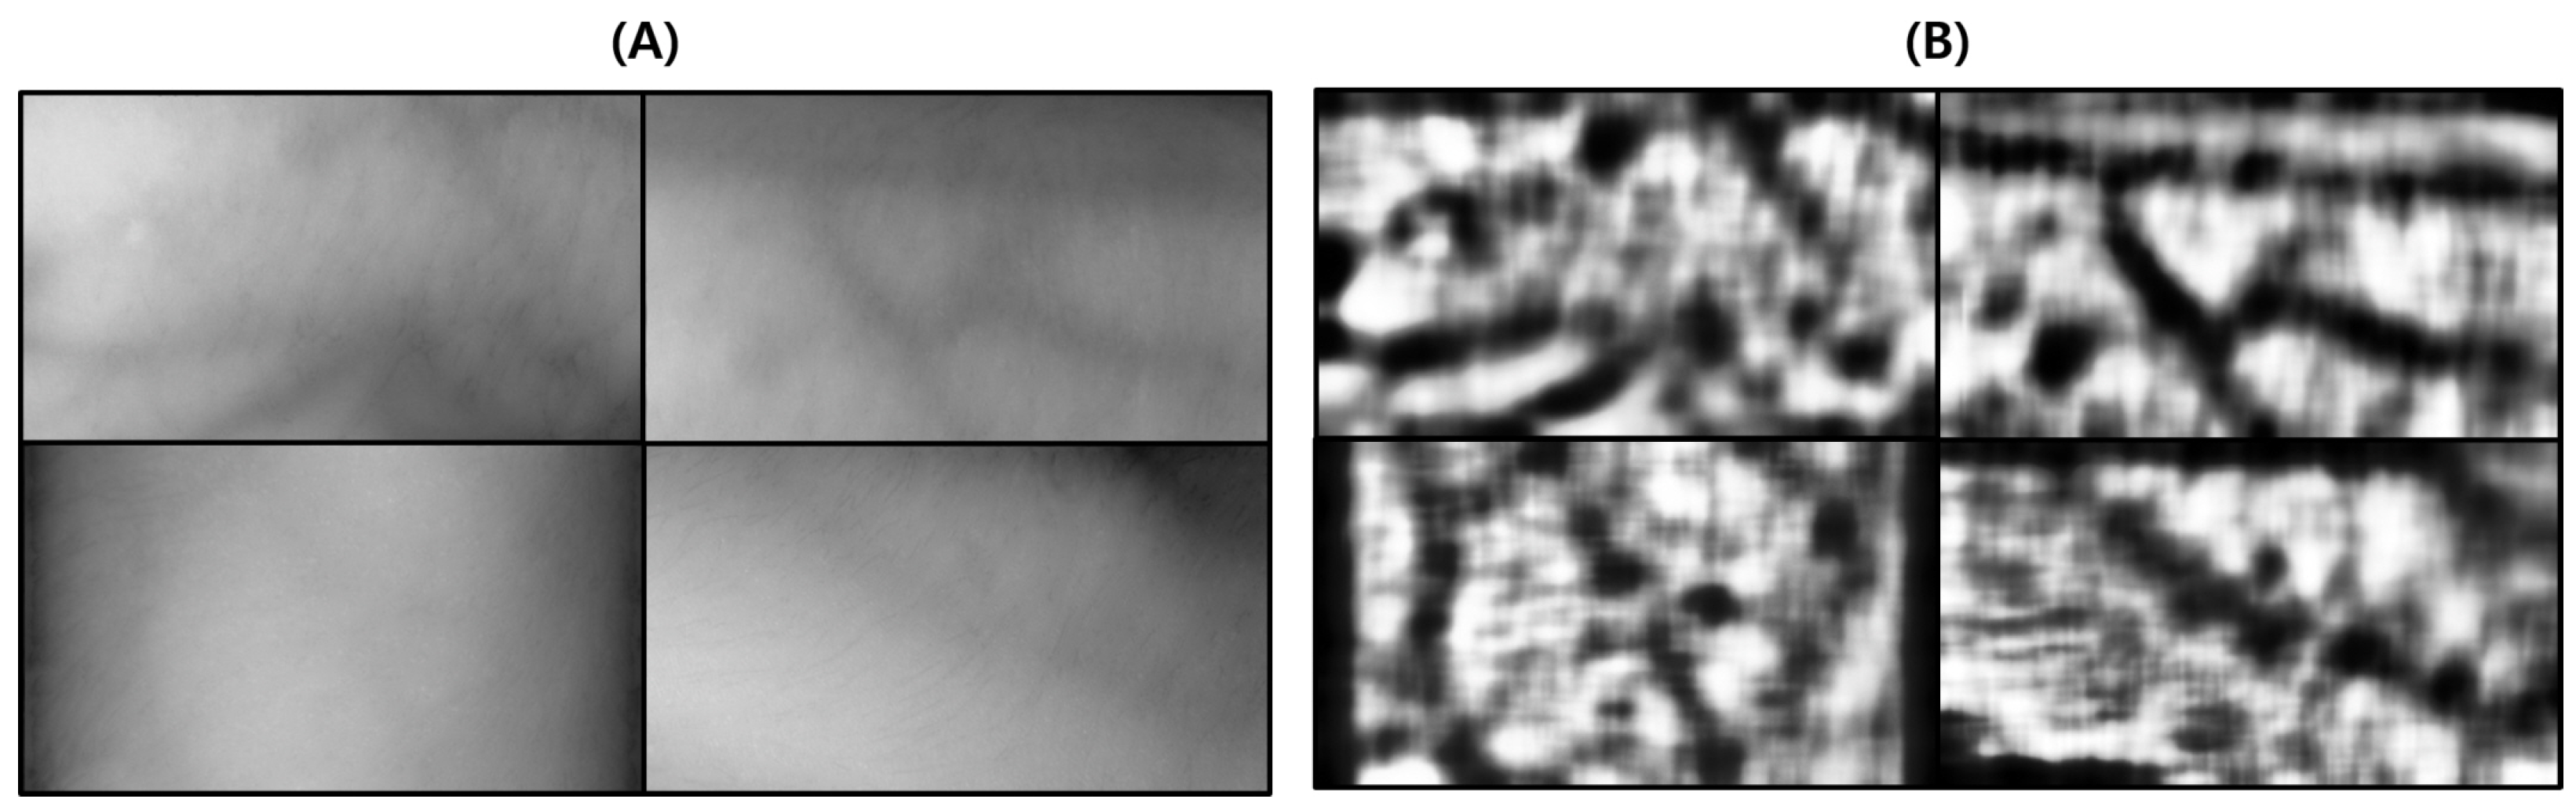

Figure 16.

Result of applying SSIM to the results of the proposed algorithm and Veinvu-100 algorithm: (A,B) are binary images obtained by applying the proposed and Veinvu-100 algorithms, respectively, and (C,D) are the results of comparing (A,B) with the vascular layer using SSIM.

As can be seen in Figure 16, in (C) overall, compared to (D), the effect of body hair noise was reduced, the contrast of blood vessels was clearer, and the cutoff or omission of blood vessels was reduced. This can be seen from the histogram of (C). In the case of (C), components other than blood vessels are removed to maximize contrast with blood vessels. A histogram distribution similar to image (B), including only the blood vessel layer, can be confirmed. On the other hand, in (D), the contrast of body hair is the strongest. As a result, the visibility of blood vessels with relatively weak contrast is somewhat less improved. It can be seen that the histogram distribution is also similar to the original image.

For objective performance verification between the proposed and Veinvu-100 algorithms, SSIM-based similarity evaluation was performed using the output images of each algorithm.

In Figure 16C, compared to (D), it can be confirmed that the overall noise was sufficiently reduced to be clearly identified with the naked eye. As a result of checking the similarity for all 10 images used in the test, the proposed algorithm measured an average SSIM of 74.93%, and the VeinVu-100 algorithm had an average of 64.55%, indicating that the proposed algorithm improved performance by 10.38% compared to VeinVu-100. Detailed verification results can be seen in Figure 17 and Table 3 below.